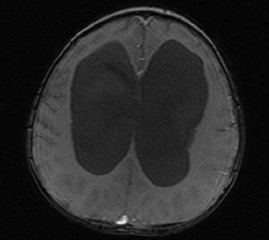

After the scan Jenifer Brown, the neurosurgeon, was round to say that the CT Scan had reviled that the fluid that was supposed to be draining was in fact pooling between his skull and his brain.

Now, although this was deemed to be bad, Jenifer had never scanned a patent after only a week, so did not know if this was just part of the normal rearranging of the brain. There is no air in your skull, so if the thin walls of Kaiden’s brain are moving around (as horrible a picture that presents) then the fluid would build there.

Jenifer opted to wait for a few days and scan him again on the Monday. If the scan showed the fluid dissipating and Kaiden was well then they would do nothing. If everything was not OK then they would operate immediately.

The took Kaiden down for a CT Scan around 12pm and we then had to wait anxiously for the results. I managed to catch a sneaky look at the scans and they looked fantastic compared to the pre-operation MRI.

When Jennifer Brown came up to see us, she said that all the fluid was being absorbed and that she could not believe the difference in Kaiden in just two short weeks. She said that we would still have little niggles for the next month or so, but that everything looked fantastic.